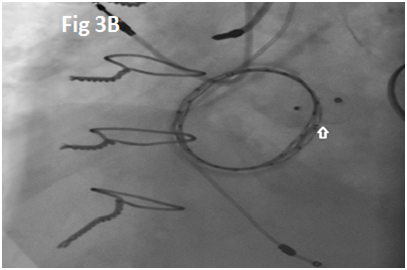

A 73-year-old female with mechanical mitral valve, tricuspid annuloplasty (32mm Edwards Physio Tricuspid incomplete ring) underwent Transcatheter Tricuspid Valve Replacement (TTVR) using off-label 29mm Edwards Sapien 3 (S3) Transcatheter Heart Valve (THV). Immediate post valve deployment, mild Perivalvular Leak (PVL) was noticed at the septal aspect (area of incomplete annuloplasty ring). Eighteen months later, patient presented with recurrent right heart failure and paracentesis due to severe tricuspid PVL (Figure 1A-C, Video 1). Percutaneous PVL closure under general anesthesia, Trans-esophageal Echocardiography (TEE) was performed. Via femoral venous access, defect was easily crossed with Agilis steerable sheath, multipurpose catheter and 0.035” glide wire. Despite recurrent attempts, wire came through the PVL but then traversed through open cells of S3 into the right ventricle (Figure 2A), confirmed with Armada 6mm balloon waist at the S3 cage (Figure 2B) (despite inflating 28mm Z med balloon inside S3 cage, Figure 2C). We decided to partially deploy the plug and assess valve function. Using 7.5F Asahi Eaucath multipurpose guide, a 12mm AmplatzerTM Vascular plug II (AVP II) was advanced through the defect. The ventricular disc was opened inside the S3 cage while body in the PVL defect (outside the S3 cage) and atrial disc on the atrial side of PVL (Figure 3A-B). With S3 function unaffected, no central leak and minimal gradient, PVL reduced to mild severity (Figure 4A-D, Video 2); the AVP II was successfully deployed (Figure 5). At 3-month follow up, there was an excellent symptomatic improvement (NYHA functional class I), with no heart failure re-hospitalization or paracentesis. Deployment of plug disc inside the valve frame is not recommended due to fear of interference with leaflet function and possible injury in long term. There was no immediate issue with the valve function in this case (due to space between the leaflet and frame of S3 and depends on size of plug used). Valve-in-Valve (S3-in-S3) would have certainly sealed all open cells treating this PVL but is more expensive option.

Figure 3 Successful implantation of AmplatzerTM Vascular plug II (white arrows).